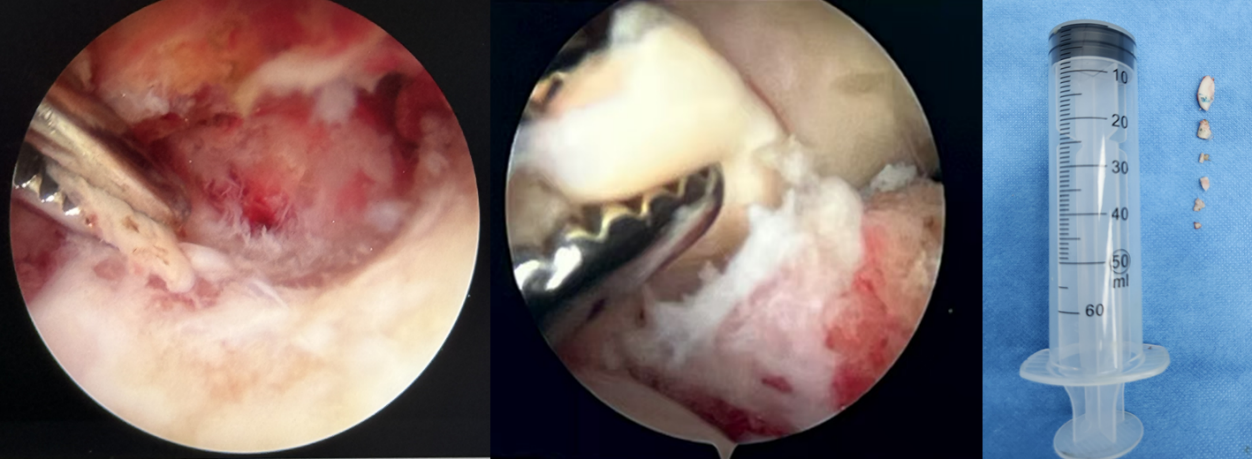

在医疗团队的精心配合下,于朱先生肘关节后方建立2个毫米级的微小切口,逐一取出多枚软骨碎片,尤其是卡压在肱尺关节深处的一枚较大游离体,这正是造成患者肘关节症状的元凶。手术全程耗时1小时余、出血仅10ml,术后即刻查体:肘关节活动度达伸直0°、屈曲130°,患者苏醒后未见神经血管并发症。目前,患者在骨科及康复医学科团队指导下正积极进行康复训练,有望完全恢复肘关节功能,重返日常的工作生活。

镜下取出多枚游离体,术后CT验证关节腔内游离体已彻底清除